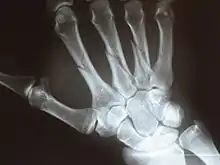

X-ray

Fracture

The neck of a metacarpal is a common location for a boxer's fracture, but all parts of the metacarpal bone (including head, body and base) are susceptible to fracture. Several types of treatment exist ranging from non-operative techniques, with or without immobilization, to operative techniques using closed or open reduction and internal fixation (ORIF). Generally, most fractures showing little or no displacement can be treated successfully without surgery.[4] Intraarticular fracture-dislocations of the metacarpal head or base may require surgical fixation, as fragment displacement affecting the joint surface is rarely tolerated well.[4]

X-ray image of right hand with thumb on left.

Multiple fractures of the metacarpals (aka broken hand). (Right hand shown with thumb on left.)